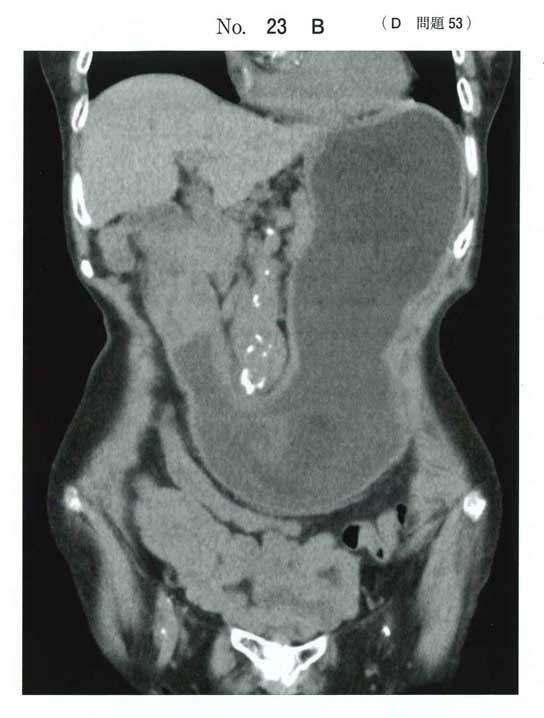

経過と腫瘍マーカー、CTで胃幽門部の壁肥厚から胃癌疑い。それで通過障害があるんですかね。

模試で出まくっていたSMA症候群な気もしますね。

CEA高値は悪性腫瘍による体重減少→二次的にSMA症候群発症の流れかなと思います。